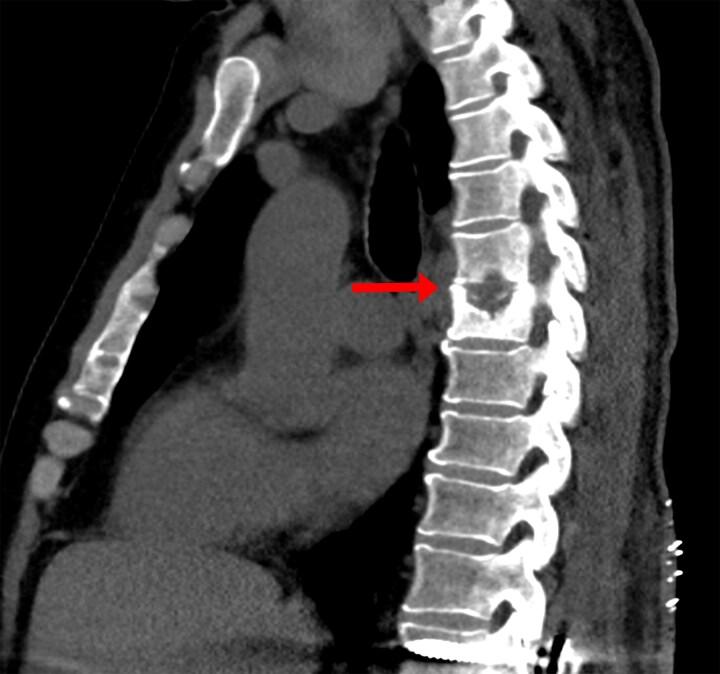

can infect the native vertebral body and nearby structures to cause tuberculous spondylodiscitis, also known as Pott disease. We present a case of extensive, multifocal Pott disease in a United States-born veteran without human immunodeficiency virus. We briefly comment on when to consider Pott disease in cases of vertebral osteomyelitis. We also discuss treatment considerations for Pott disease with and without tuberculous involvement of the central nervous system, the recognition of tuberculosis-associated immune reconstitution inflammatory syndrome, and certain indications for surgery in Pott disease.

可感染原生椎体及附近结构,导致结核性脊椎间盘炎,也称为波特病。我们报告一例在美国出生、无人类免疫缺陷病毒的退伍军人发生广泛、多灶性波特病的病例。我们简要评论在椎体骨髓炎病例中何时应考虑波特病。我们还讨论了波特病伴或不伴有中枢神经系统结核感染时的治疗考量、结核相关免疫重建炎症综合征的识别以及波特病的某些手术指征。